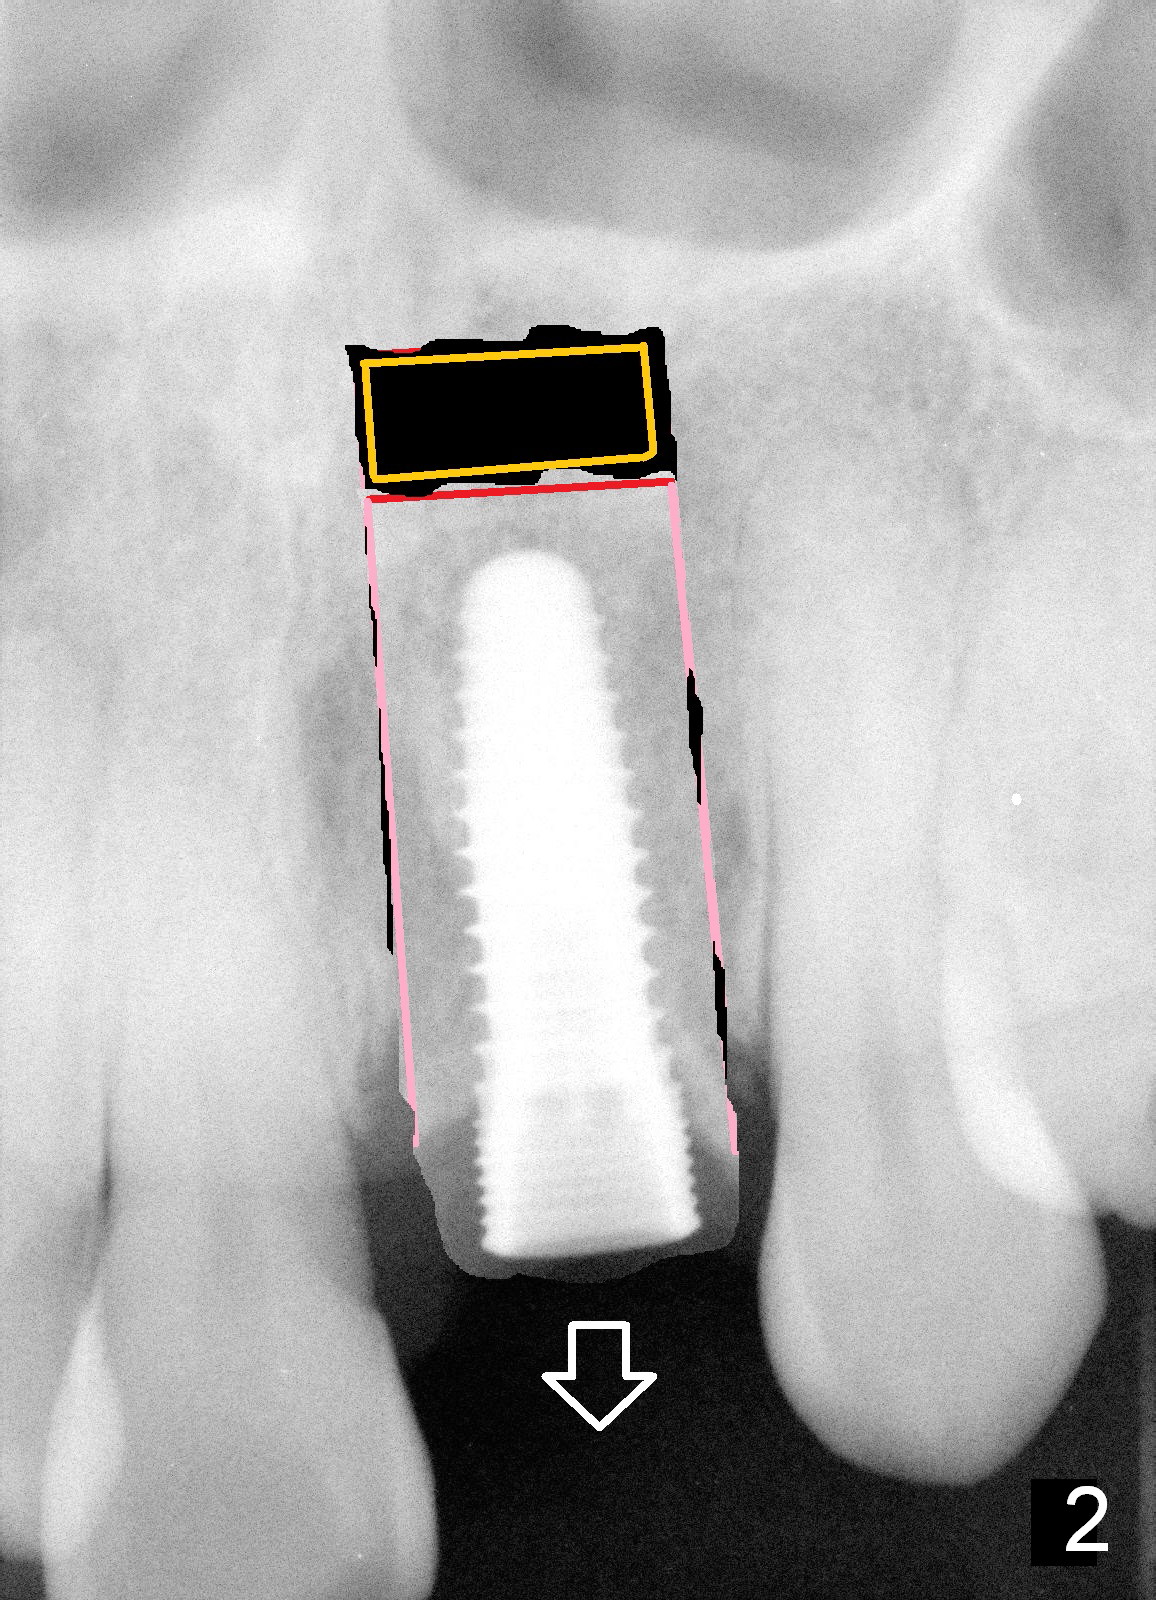

Immediate implant allows an anterior implant to be placed away from the nasal floor (Fig.1 arrowheads). In case the implant needs to be repositioned after osteointegration, there is room for a transverse cut (red line: vertical cut: pink). When the implant bony segment moves coronally (Fig.2 arrow), a block graft is inserted in the apical space (yellow) to prevent relapse.